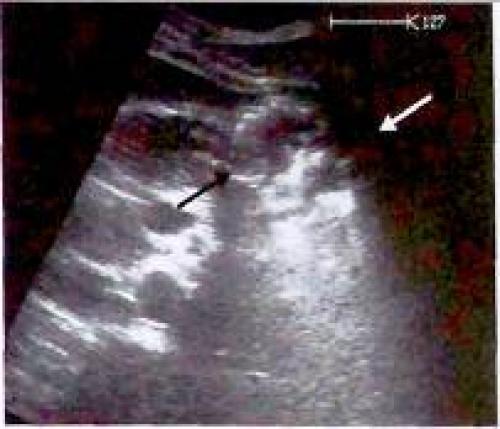

К структурам, которые, как правило, хорошо видны при ультразвуковом исследовании, относятся кардия и гастроэзофагеальный переход, антральный отдел желудка, а также двенадцатиперстная кишка. При этом печень играет роль ультразвукового окна. Качество же визуализации дна и тела желудка спереди или через селезенку (ультразвуковое окно) оставляет желать лучшего. Кардиальный отдел желудка чаще и лучше всего удается визуализировать на продольном сечении, когда желудок определяется между печенью и аортой.

Рис. 3. Визуализация гастроэзофагеального перехода на продольном сечении

Рис. 4. Визуализация гастроэзофагеального перехода на поперечном сечении: Виден срез тела желудка, заполненного неоднородным содержимым (v

В качестве примера патологии кардиального отдела желудка, выявляемой сонографически можно привести его карциному (Рис 5).

Рис 5. а, b Гастроэзофагеальное сочленение (включает кардиальный отдел и входной отдел желудка), а На снимке в косой продольной плоскости, проходящей через верхнюю часть брюшной полости, определяется нормальная гипоэхогенная стенка (мышечный слой) кардиального отдела и свода желудка, b Карцинома кардиального отдела желудка: неправильной формы, гипоэхогенное опухолевое образование, продолжающееся от кардиального отдела пищевода (ES) до свода желудка (F). АО - аорта.

Визуализация тела желудка на продольном сечении

У неподготовленного к обследованию пациента тело желудка визуализируется только как постоянно изменяющееся поле позади левой доли печени. При имеющемся исходном изображении гастроэзофагеального перехода найти эту область достаточно просто.